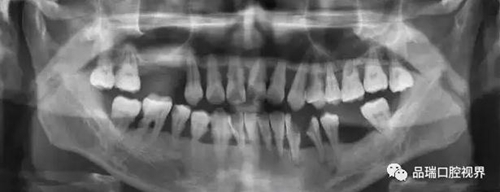

牙周炎是由于牙結石過多刺激所引起的。對于牙周炎的治療,可以通過洗牙去除牙結石從根本上預防牙周炎的發生。但事實上,當大家說起“潔牙”時,許多人的內心確實是矛盾的。一方面,深深地明白一年1-2次的潔牙是口腔健康的必備作業。但另一方面,潔牙時產生的酸痛和不適感卻又讓人覺得不那么愉快。

刷牙出血、牙齦紅腫、疼痛,這種情況幾乎人人都有過。在疲勞、生活不規律,刷牙潦草時更容易出現。很多朋友以為牙齦出血是因為缺乏某種維生素。其實,雖然長期嚴重缺乏維生素C確實會導致牙齦出血紅腫,但除非一連兩三個月都不吃蔬菜水果牛奶等含有維生素C的食物,否則,除了極少數人是由于血液病等全身疾病,絕大多數牙齦出血都是牙齦炎的表現。牙齦出血,原因多為牙齦炎或牙周炎。

牙周炎是一種漸進性的疾病——就是說它并不會像普通感冒一樣,不管治不治療,只要不繼發感染,一周左右都會好。如果不對炎癥和口腔的刺激因素進行控制,牙齦炎會進一步發展為牙周炎,這就不再是僅限于軟組織的炎癥,而是會累及牙槽骨,當骨質緩慢喪失,牙齒就失去了支撐,開始松動,最終導致牙齒脫落。